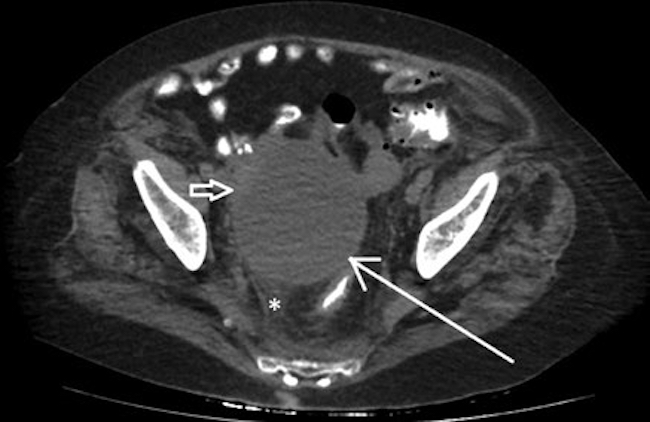

Dados los hallazgos ecográficos, se realizó una tomografía computada abdominal y pélvica, en la que se observaron una solución de continuidad de 22 mm en el flanco izquierdo (Fig. 1) y una imagen ovalada ligeramente edematizada (Fig. 2). En la cavidad pelviana se observó una imagen líquida de aspecto quístico de 91 × 87 × 81 mm, dependiente de anexo derecho (Fig. 3). Durante su internación, la paciente persistió con dolor a nivel referido y fue llevada a laparotomía exploratoria, en la que se halló un tumor abscedado sobre la aponeurosis del músculo oblicuo izquierdo, del que se tomaron muestras para anatomía patológica, y se drenó y corrigió la solución de continuidad en el acto quirúrgico. Se amplió el estudio microscópico con marcadores tumorales CA 125 y CA 19-9, que fueron positivos para metástasis de carcinoma primario de ovario (Fig. 4). Actualmente, la paciente está en manejo oncológico.